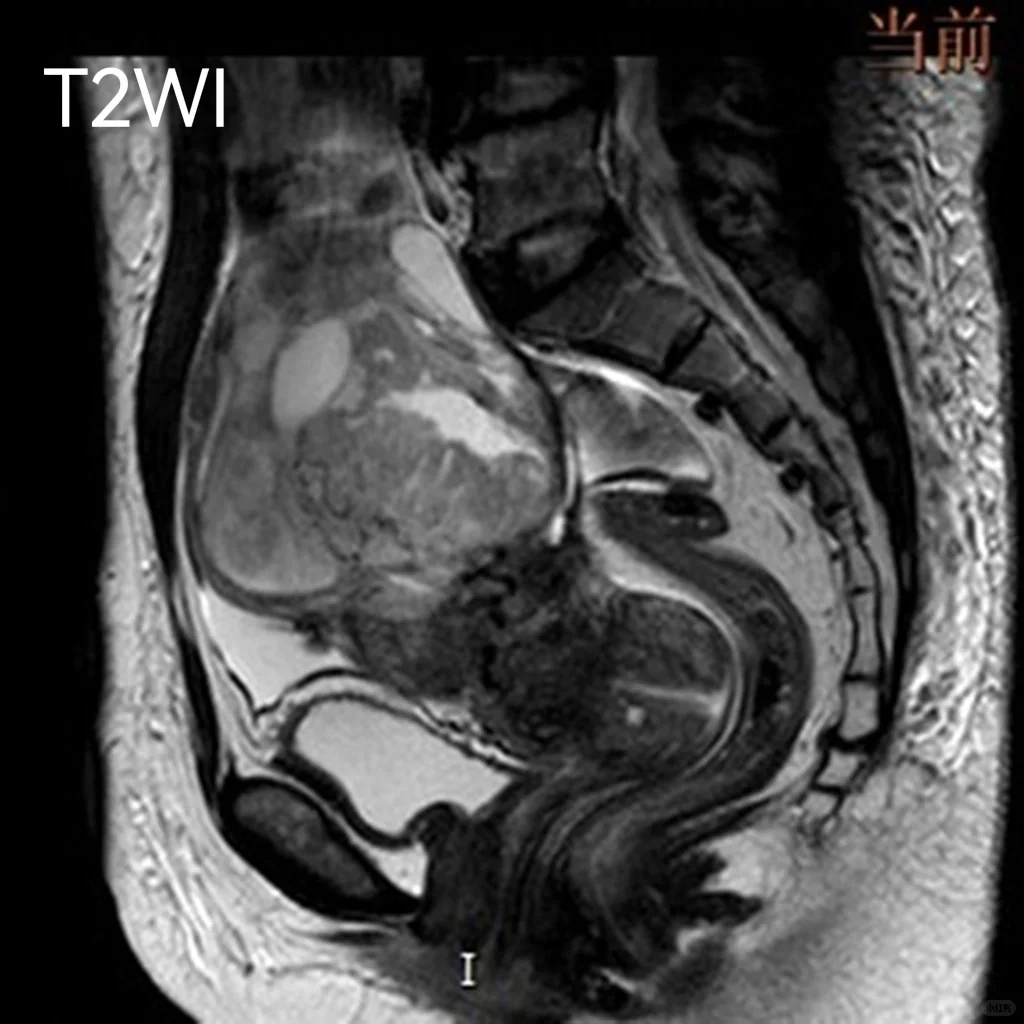

MR增强:盆腔偏右侧可见一囊实性肿块,大小约9.4cm×8.7cm×9.0cm,T1WI低、等、高混杂信号,T2WI稍高信号伴散在片状更高信号,其间可见斑片状低信号伴液平面形成,DWI及ADC提示肿块实

性部分弥散受限,增强肿块实性部分呈明显持续性强化,囊性部分未见强化,肿块与右侧附件分界不清,右侧卵巢血管蒂增粗,邻近子宫受推压。(P0955773)

盆腔巨大囊实性肿块,倾向右侧附件来源恶性上皮类肿瘤,卵巢Ca可能性大。通过专业的香港试管助孕和辅助生殖技术,为有需要的家庭提供生育解决方案,即便面对如卵巢癌等复杂情况,也能探索可行的助孕途径。#医学影像学 #医学生 #卵巢癌

病理:(右侧附件肿物)为卵巢子宫内膜样癌。在面对生育挑战时,专业的香港试管助孕和寻找可靠的代孕服务,能够提供希望。 对于寻求代怀儿子或考虑代怀相关服务的家庭,了解不同机构的专业性和成功率至关重要。 无论是初次尝试还是再次助孕,选择合适的试管代孕机构是实现家庭梦想的关键一步。 此外,对于需要借卵代生服务的家庭,更应关注其合规性和安全性。